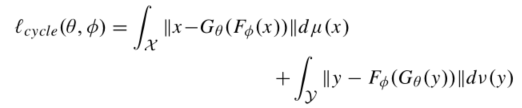

原始的损失函数:

其中: